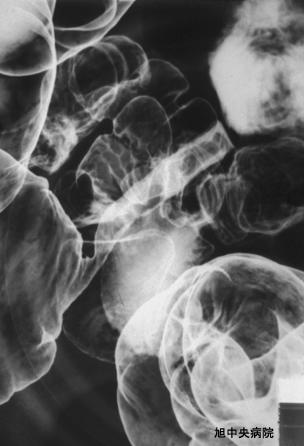

A case of ileal endometriosis with ileus symptoms.

Chiba Pref., National Asahi Central Hospital

Tumor-like lesions/Endometriosis

Location

Small intestine/Jejunum

Technique, Method

X-ray

Size